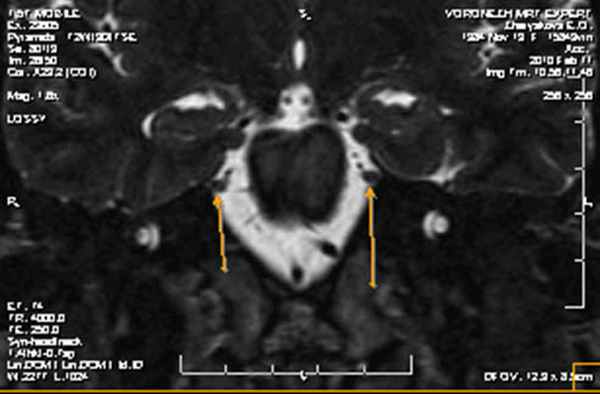

На корональной томограмме с обеих сторон хорошо видны тройничные нервы

На аксиальной и сагиттальной томограммах четко визуализируется правый тройничный нерв и прилегающая к его верхнему контуру правая верхняя мозжечковая артерия